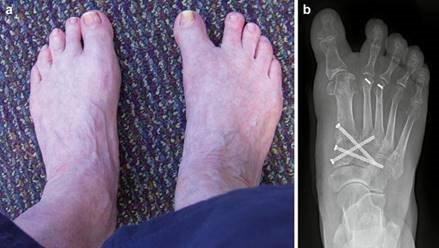

Clinical & Radiographic Imaging Archive